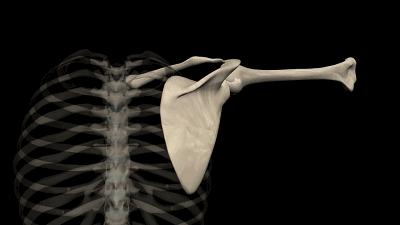

肩部三角区:纠姿势,减酸痛

肩三角相当于上臂肩关节三角肌的位置。这个区域肌肉厚实,三角肌从前、外、后三面包绕肩关节,腋神经分布于其中,支配着三角肌的收缩和舒张。

不过肩关节结构比较松散,容易因肌肉瞬间拉伤而损伤肩部软组织;上身各种运动常会使用肩关节,如果过度使用,周围的软组织会受到磨擦,易发生慢性劳损或软组织炎症。

高危因素

长时间用电脑或坐着学习的人,肩胛肌肉劳损。

单肩背、斜挎背等不当的背包姿势会引发肌肉酸痛。

睡姿不正确,可能无法维持脊背的自然曲线。

穿鞋不对。高跟鞋、人字拖会改变身体平衡,脊椎受力不均,加重后背疼痛。

专家建议

避免一个姿势保持过久,常站起来绕肩。

背包时最好双肩,不要长时间背重物。

运动前要充分热身,运动量要适度,运动中关节保持微弯,避免对抗的阻力伤及关节。